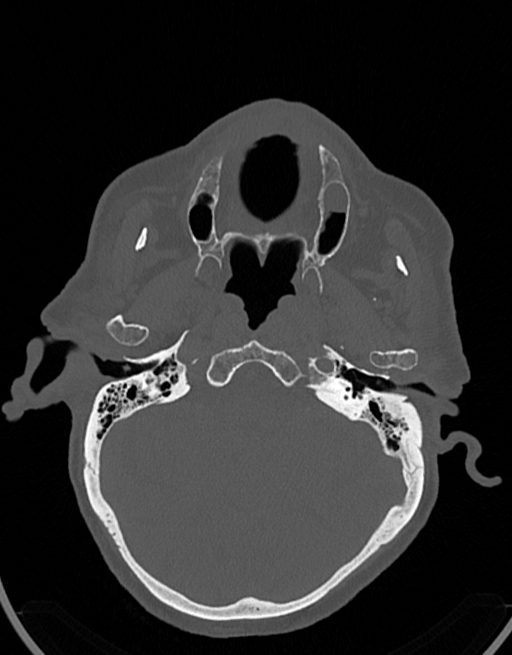

در سي تي اسکن اسپيرال نازو فارنکس با و بدون کنتراست (مولتي ديدکتور 16 با مقاطع ظريف و بازسازي هاي ساژيتال و کرونال):

– توده نسج نرمي به ابعاد mm 40 x 45 x 60 در ناحيه پاروتيد راست، با enhancement هتروژن پس از تزريق کنتراست مشهود است که مطرح کننده آدنوم پاروتيد مي باشد.

– شواهدي از تهاجم توده به استخوان و عروق اطراف مشهود نيست .

– کلسيفيکاسيون در ديواره شريان هاي کاروتيد دو طرف مشهود است .

– بررسي بافتي توده پاروتيد راست پيشنهاد مي شود .